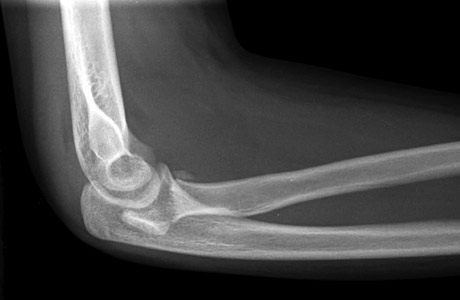

The radial head should point to the capitellum in all views (Figure 3).

Radialneck_figure_3_radiocapitellar_line_lat.jpg     Radialneck_figure_3_radius_capitellum_line_ap.jpg

Figure 3: A) Lateral view B) AP view